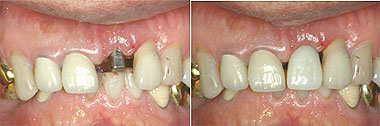

![]() ▲初期固定良く植立できた1ピースでは審美目的でTekを入れることが可能だ |

![]() ▲1ピースでは天然歯の通常のCr-Brと同様な形成印象で補綴物を作ることができる |

1ピースの場合で、欠損が前歯部のみで臼歯部は天然歯がある場合は、植立直後にアルジネート印象を採り、その模型でTekを作り、通常は翌日洗浄時にTekを仮着セメント(EZやプロパック)でセットする。どうしてもすぐにTekが欲しい患者さんには植立後30~40分待っていてもらえば作ることができる。このTekはあくまでも審美目的のもので、咬合させるためのものではないことを患者さんによく理解させ、対合歯とは咬合接触させず仮着セメントを使用し、もし強い外力が作用した時は脱離するようにしておくことが重要である。早期にTekという歯の形態に近いものが入ることにより、抜糸して数日後から術後のスーパーソフトブラシによって通常の天然歯に準じたブラッシングが可能となるので、早く歯肉が引き締まり、最終的な歯肉形態になると思われる。